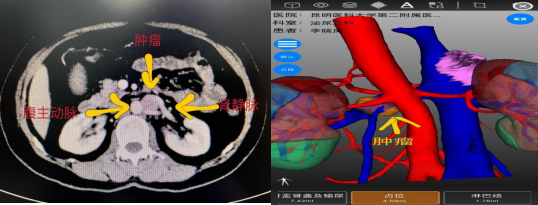

术前影像学检查

该患者既往行左肾上腺解剖性切除术,本次体检发现左侧腹膜后占位性病变,发现后患者在家人的陪伴下慕名前来昆明医科大学第二附属医院泌尿外科二病区杨德林教授门诊就诊。患者入院后,杨德林主任团队对其病情进行详细研判后发现,该占位性病变位置非常特殊,位于腹主动脉、左肾静脉、左肾动脉之间,与左肾静脉关系尤为密切,肿瘤位置较深,周围血管关系复杂,手术难度极大,术中稍不注意就可能导致周围血管的损伤从而影响重要器官的功能。若从肿瘤位置观察经腹膜后可能相对更好显露,但患者既往有手术病史,经腹膜后途径可能粘连严重。因此,经过综合考量后,团队决定积极做术前准备,手术采用机器人辅助下经腹入路。